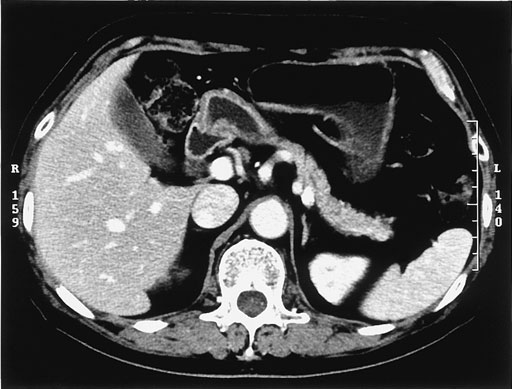

No.11症例3:66歳,男性

膵腫瘤,全身倦怠感

前立腺肥大症のため受けた超音波検査で偶然膵腫瘤を指摘され精査目的で来院した.

3年前に前立腺肥大症及びシェーグレン症候群で加療を受けている.

Amy 302 IU/l (51-226), Na 128 mEq/dl (135-147), K 3.5 mEq/dl (3.5-4.6), Cl 97mEq/dl(100-108)

• 図3 腹部CT